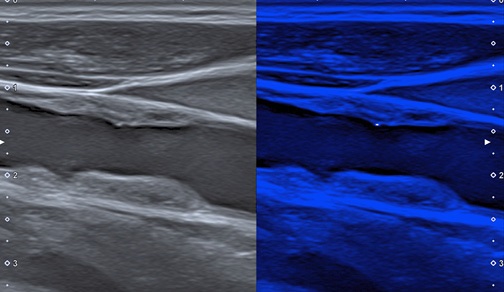

Рис. 3. Ультразвуковое изображение АСБ с единичным МК в покрышке в режиме MicroPure.

Примечание: цветное изображение доступно в электронной версии журнала.